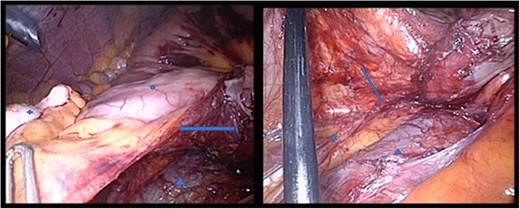

The patient was positioned supine. We used a 12-mm umbilical camera port, and 5-mm trocars were placed in the left and right middle abdomen. Laparoscopic inspection revealed a hernia aperture below the terminal ileum, behind which we found the hernia sac where the small intestine had become entangled 3 weeks previously (Fig. 3). The subsequent small bowel revision was uneventful. In the area of Treitz’s ligament, the vessels were on the right side with no herniation on the left side (Fig. 4). At this point, we decided to enlarge the hernia aperture by mobilizing the cecum. The ureter and the testicular vessels were identified. Finally, the hernia sac was widened, to prevent future entrapment of the small intestine. (Fig. 5) The postoperative course was uneventful and the patient was discharged 2 days later.

Star: transverse colon under the greater omentum, arrow: vessel axis, circle: proximal jejunum. The ligament of Treitz is not shown

Both pictures display the hernia sac; in the right panel, the hernia sac has been elevated. Circle: terminal ileum, cross: appendix, star: ureter, triangle: V. cava, arrow: hernia sac, which has been opened